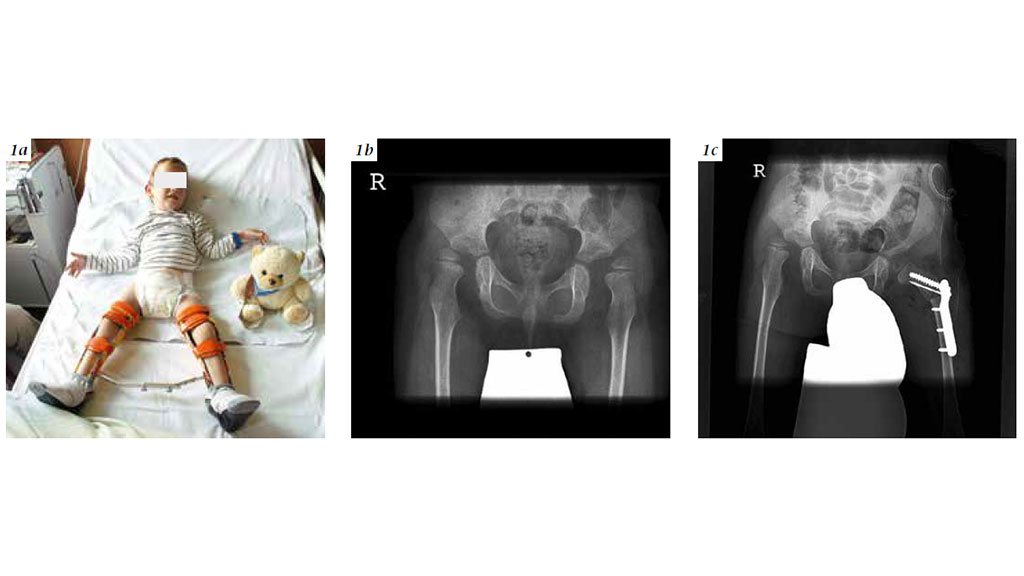

Umgekehrt ist die Orthopädie-Technik unverzichtbar, um operative Maßnahmen zu begleiten. Bei der Rezentrierung des Hüftgelenkes nach einer neuromuskulär bedingten Hüftluxation etwa ist eine Hüftlagerungs- bzw. Hüftabduktionsorthese postoperativ erforderlich (Abb. 1a – c). Auch bei den Operationen, die die Funktion verbessern sollen, sind postoperativ Lagerungsorthesen oder die funktionsunterstützenden Orthesen zur verbesserten Kniestreckung oder Fußabstützung sehr wichtig.